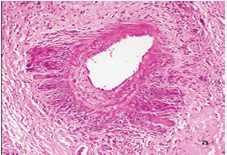

The infiltrates surrounded several neural bundles, which had dissociated perineurium (Figure 3,4).

Figure 3a A nerve in the center of the figure has dispersed perineurium and is surrounded by a giant cell. The peripheral infiltrate has many giant cells with numerous nuclei, lymphocytes and eosinophils.

Figure 3b These nerves (lower right B) have no defined perineurium and are surrounded by diffuse infiltrate of macrophages, giant cells, lymphocytes and eosinophils.

Figure 3c These nerves have no defined perineurium and are surrounded by diffuse infiltrate of macrophages, giant cells, lymphocytes and eosinophils. Vacuolated macrophages seem to be endoneural.

Figure 3d This nerve does not show perineurium and is surrounded by prominent giant cells, but looks well preserved. A-D: HE. A, B: 16 X. C, D: 40 X.

Figure 4a This nerve is surrounded by granulomas and lymphocytes but its structure looks normal.

Figure 4b It is not easy to determine if this nerve is being infiltrated and destroyed by the cellular reaction or if it is simply surrounded by it.

Figure 4c Well preserved nerve with a giant cell, scant macrophages and some lymphocytes in the endoneurium. A-C: HE. A,10 X. B, 16 X. C, 40 X.

Some giant cells and macrophages touched the nerve or penetrate the endoneurium and distorted neural architecture (Figures 3,4). Other cutaneous nerves were located at the center of the infiltrate and looked well preserved (Figure 5).